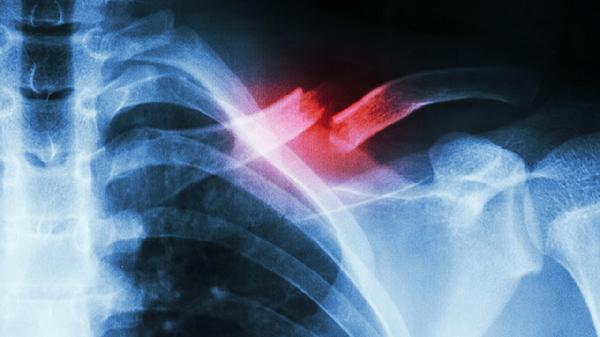

术后1周需拍摄X线片观察对位情况,3个月后复查CT评估愈合进度。多发性骨折可能损伤胸膜导致血气胸,表现为突发胸闷,需紧急行胸腔闭式引流术。恢复期间避免提重物及剧烈运动,睡眠时采取半卧位减轻胸部压力。